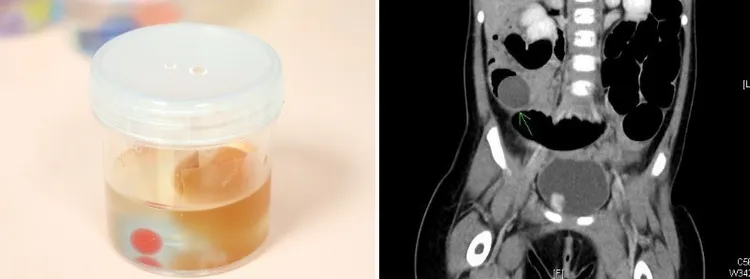

經安排X光、電腦斷層等檢查,賴宛孜發現男童小腸有多段腫脹現象,會小兒外科醫師蔡逸文為男童開刀。蔡逸文指,經剖開男童小腸段,發現裡面有多顆脹大的水晶寶寶,已將小腸阻塞,其中最大一顆橢圓形水晶寶寶,竟然有2乘以3公分大,這是男童為何會嘔吐、吃不下原因,取出腸內異物後,留男童住院觀察。

男童術後一度可進食,但2、3天後,又開始嘔吐、吃不下,賴宛孜再為男童檢查,發現還有水晶寶寶阻塞住腸道,因此在術後第5天,由蔡逸文再為男童開第2次刀。

蔡逸文說,第2次手術時,他發現男童的小腸又出現新的阻塞段,「腸子鼓地大大的」,一樣剖開後看到多顆已膨脹的水晶寶寶。

「到底還有多少的水晶寶寶?」望著手術抬上被全身麻醉的男童,也進開刀房的賴宛孜,決定以胃鏡直趨男童胃的底部,內視鏡影像中看到一堆水晶寶寶的凝膠殘塊,這些難以計數的「水晶寶寶」,都可能再脹大,等通過男童小腸再造成阻塞。